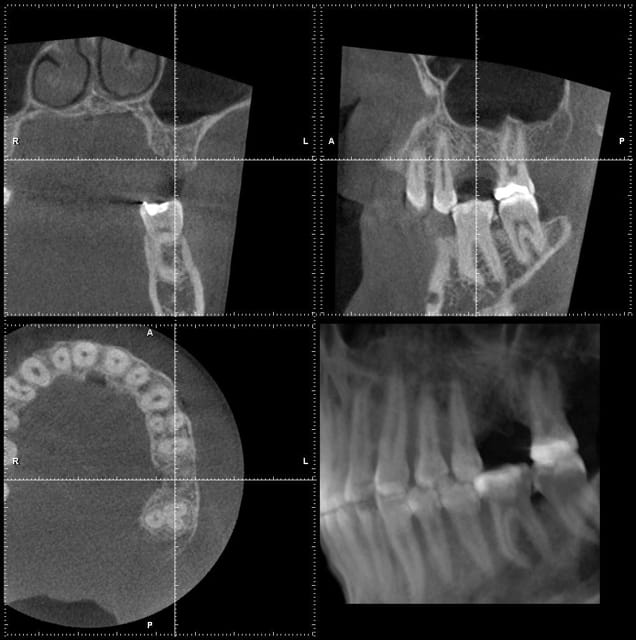

les premières copies d'écran (je ne maîtrise pas encore le logiciel)